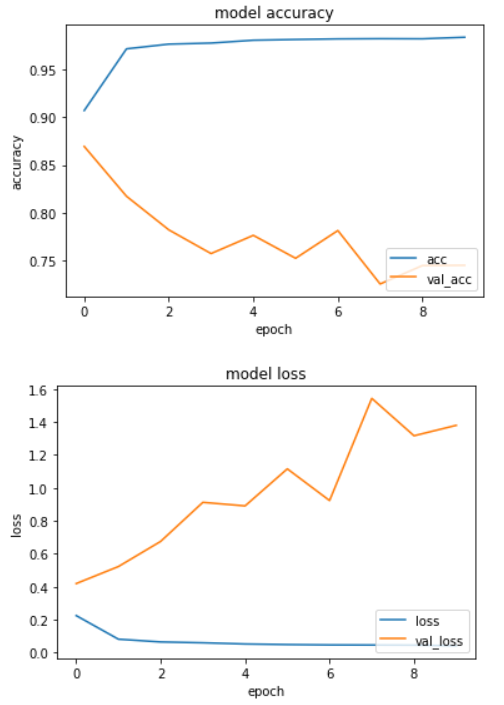

計算の状況を確認します。accurasyとlossをグラフ化してみました。

def plot_history(history): plt.plot(history.history['acc']) plt.plot(history.history['val_acc']) plt.title('model accuracy') plt.xlabel('epoch') plt.ylabel('accuracy') plt.legend(['acc', 'val_acc'], loc='lower right') plt.show() plt.plot(history.history['loss']) plt.plot(history.history['val_loss']) plt.title('model loss') plt.xlabel('epoch') plt.ylabel('loss') plt.legend(['loss', 'val_loss'], loc='lower right') plt.show() plot_history(training)

少しオーバーフィッティング気味かなという印象を受けます。